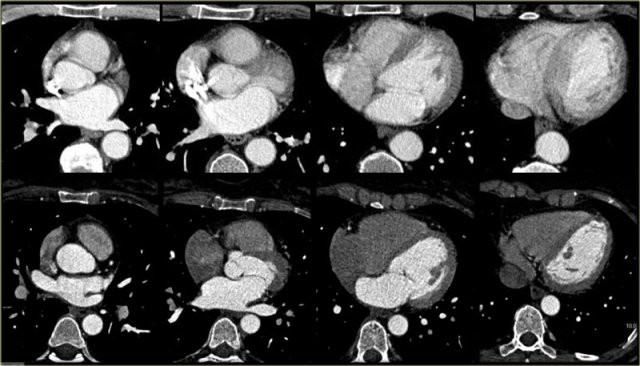

Cardiac CT with ECG triggering offers good image quality of the heart when compared to CT performed for other purposes.

As in any other field of radiology, analysis of the acquired images requires a systematic approach.

Axial slices, such as those imaged on the left, are useful for a global assessment of the morphology of the heart and its relation to the pericardium.